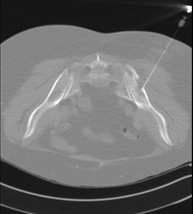

- CT-guided thoracic FNA (fine needle aspiration)

This test obtains a sample of tissue from thoracic lesions, such as lung masses, mediastinal masses, bone lesions, etc. This test is performed using local anaesthesia on the puncture area, which is administered with fine-gauge needles. The entire procedure is performed with guidance from images obtained by computed tomography (CT) at various stages of the puncture, using fluoroscopy-CT equipment. After the test, the patient remains in hospital for a few hours. Coagulation tests must be performed before the puncture.

- CT-guided thoracic biopsy

It consists of obtaining a tissue sample from a specific thoracic lesion, such as the lung, mediastinum, sternum, etc. It is sometimes performed under sedation with the help of an anaesthesia team. Needles are used to draw a cylinder sample from the lesion to be studied, which is then sent to the Pathology Department for histological analysis. The entire procedure is performed with guidance from images obtained by computed tomography (CT) at various stages of the biopsy, using fluoroscopy-CT equipment. After the test, the patient remains in hospital under observation. Coagulation tests must be performed before the puncture.